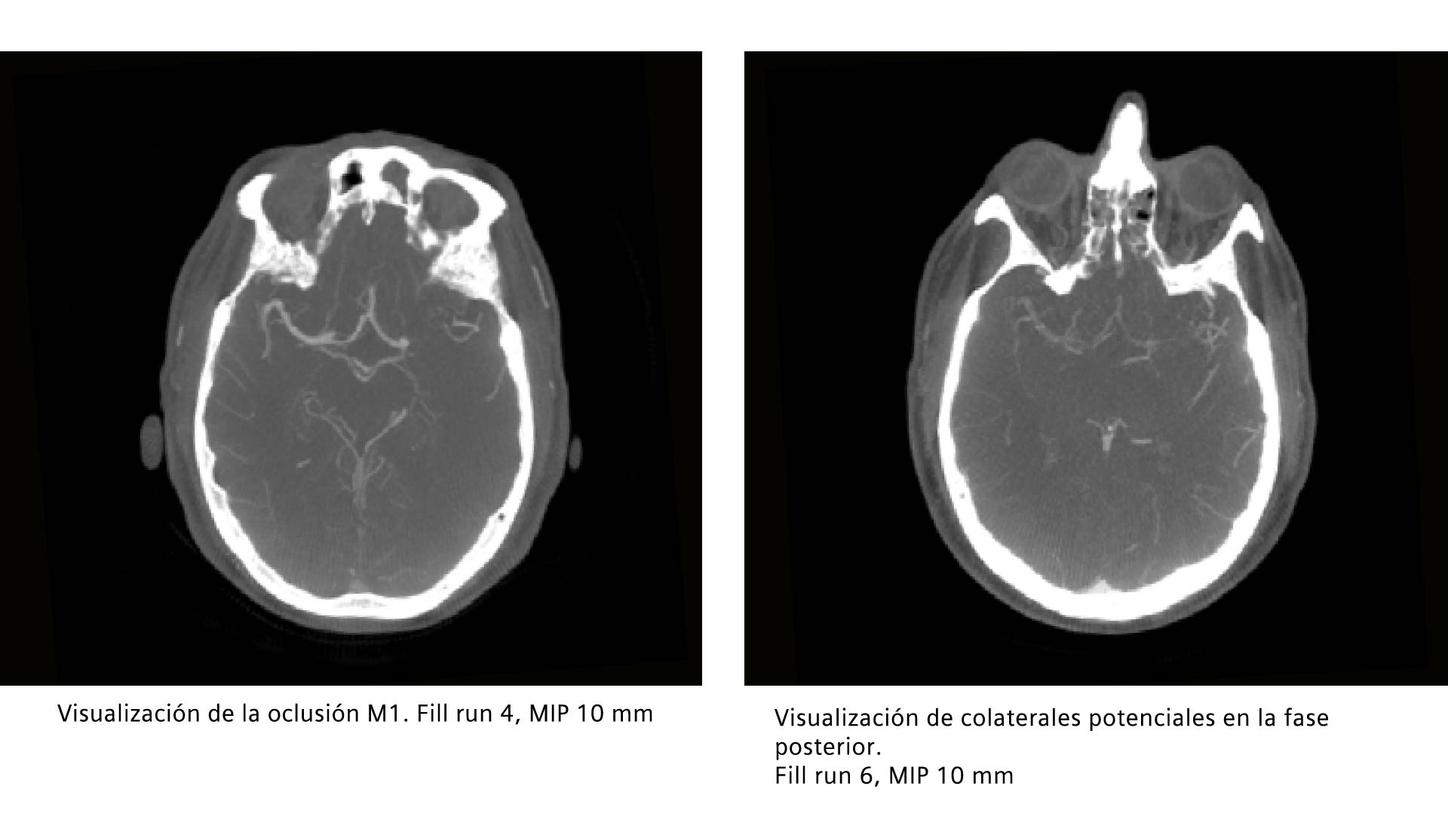

Oclusión de la M1 en el lado izquierdo debido a una estenosis aterosclerótica intracraneal subyacente.

El syngo DynaCT Multiphase consta de 10 rotaciones consecutivas que dan como resultado 10 volúmenes. Comience la inyección con el inicio de la adquisición de la serie. Los primeros dos volúmenes se requieren como serie de máscara para la posible reconstrucción de los mapas de perfusión.* Los otros 8 volúmenes son series de llenado.

Primera ejecución de syngo DynaCT Multiphase antes de la trombectomía